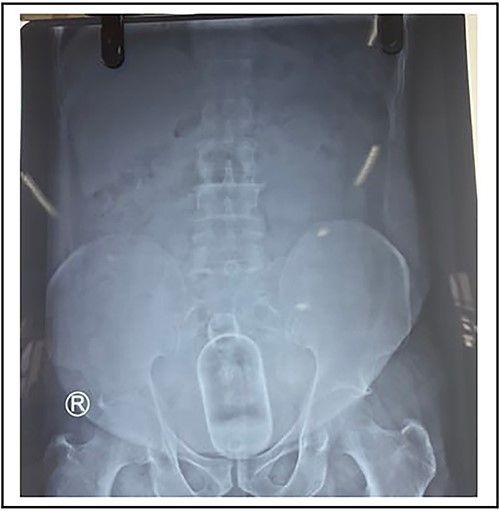

The rectal foreign body is a rare presentation at the Emergency Department. Whatever may be the motive whether it’s sexual gratification, concealment, body packers, sexual assault and, rarely, accidental the mortality and morbidity is high in the rectal foreign body as they only present for medical attention after several unsuccessful attempts to remove the object alone due to embarrassment. The standard technique for the trans-anal approach involves the combined use of analgesia, sedation, anesthesia and an attempt at manual removal of the foreign body. We hereby present a case of a male who was referred to the Emergency Department with a cough syrup bottle in his rectum. A 58-year female was admitted in emergency with a foreign body stuck in the anal canal for 24 h. He is a known case of psychiatric illness not under medication. It was acute in onset that happened while he was scratching his anal area with a cough syrup bottle. Following insertion, he developed severe pain and was unable to pass stool flatus; however, there was no per rectal bleed. He gives no history of past medical or psychiatric illness. His vitals were within normal limits and systemic examination was within normal limits. At emergency X-ray of the abdomen and pelvis was done, which showed a foreign body in the anal canal (Figs 1 and 2). Blood investigations were within normal limits. Digital rectal examination was done; however, no mass or foreign body was palpable. The patient underwent emergency manual removal of the foreign body via obstetric forceps under general anesthesia. Operative findings showed a foreign body (cough syrup bottle) of size 10 cm × 15 cm in the distal rectum about 8 cm above the anal verge (Fig. 3). The patient developed severe pain and stool incontinence and so was admitted at the ward and kept under observation. Psychiatric and cermatology consultation was done and the patient was discharged on the second postoperative day under oral medication. Sigmoidoscopy was done on a follow-up, which showed normal findings with minimal mucosal tear without perforation.

X-ray showing abdomen and pelvis with foreign body with no signs of perforation.